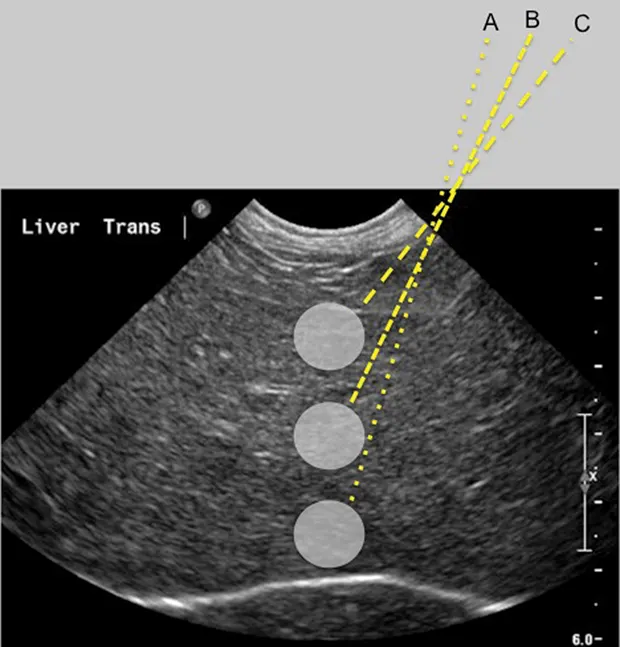

Step-by-Step: Ultrasound-Guided Fine-Needle Aspiration Cytology of the Liver

Prepare the area. If the patient is not already clipped, clip and clean the sampling area; consider a surgical scrub if the skin is particularly dirty or a sample will be submitted for culture. Remove ultrasound gel applied to the area, as it can create an artifact on the slide to be viewed by the pathologist.

Leave the area wet with alcohol or liquid (not jelly) lidocaine as a contact medium for the ultrasound transducer. Clean the transducer by placing an alcohol gauze sponge on the transducer tip while preparing the patient.